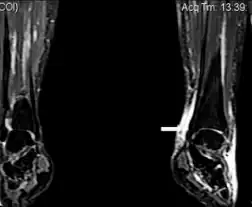

| Image with extensive epifascial edema in left foot of individual with secondary lymphedema | |

Secondary lymphedema is a condition characterized by swelling of the soft tissues in which an excessive amount of lymph has accumulated, and is caused by certain malignant diseases such as Hodgkin's disease and Kaposi sarcoma.[2]: 849

Secondary lymphedema also can be caused by several non-malignant diseases, such as lipedema, and can result from the removal of lymph nodes during various cancer surgeries, especially for breast and prostate cancers.